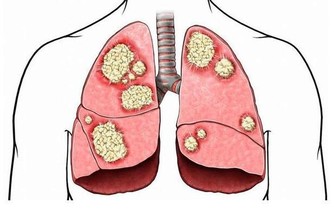

長期睡眠不足,容易影響神經中樞,干擾內分泌,影響免疫機制,從而使人更易患上癌症。

事實上,已有多項研究表明,長期睡眠不足,患結直腸癌、甲狀腺癌、肺癌等癌症的風險都會增加。

研究發現,與睡眠時間為7小時者相比,睡眠不足者(≤5小時)發生結直腸癌的風險增加36%。

相比較少失眠的女性,經常失眠的女性發生甲狀腺癌的風險要高出44%。

相比睡眠時間在7~7.5個小時的男性,睡眠不足(≤6.5小時)的男性,發生肺癌的風險增加112%。